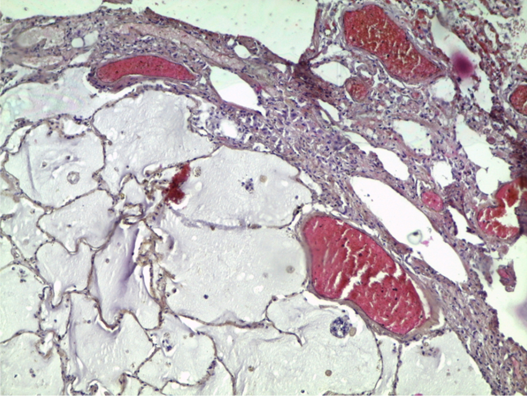

Препарат № 380.

МЕТАСТАЗ МУЦИНОЗНОЙ АДЕНОКАРЦИНОМЫ В ЛЕГКОЕ

Окраска: гематоксилин-эозин

В ткани легкого – опухолевый узел слизеобразующей (муцинозной) аденокарциномы.

Отметить:

1. Метастаз аденокарциномы

2. Слизь.